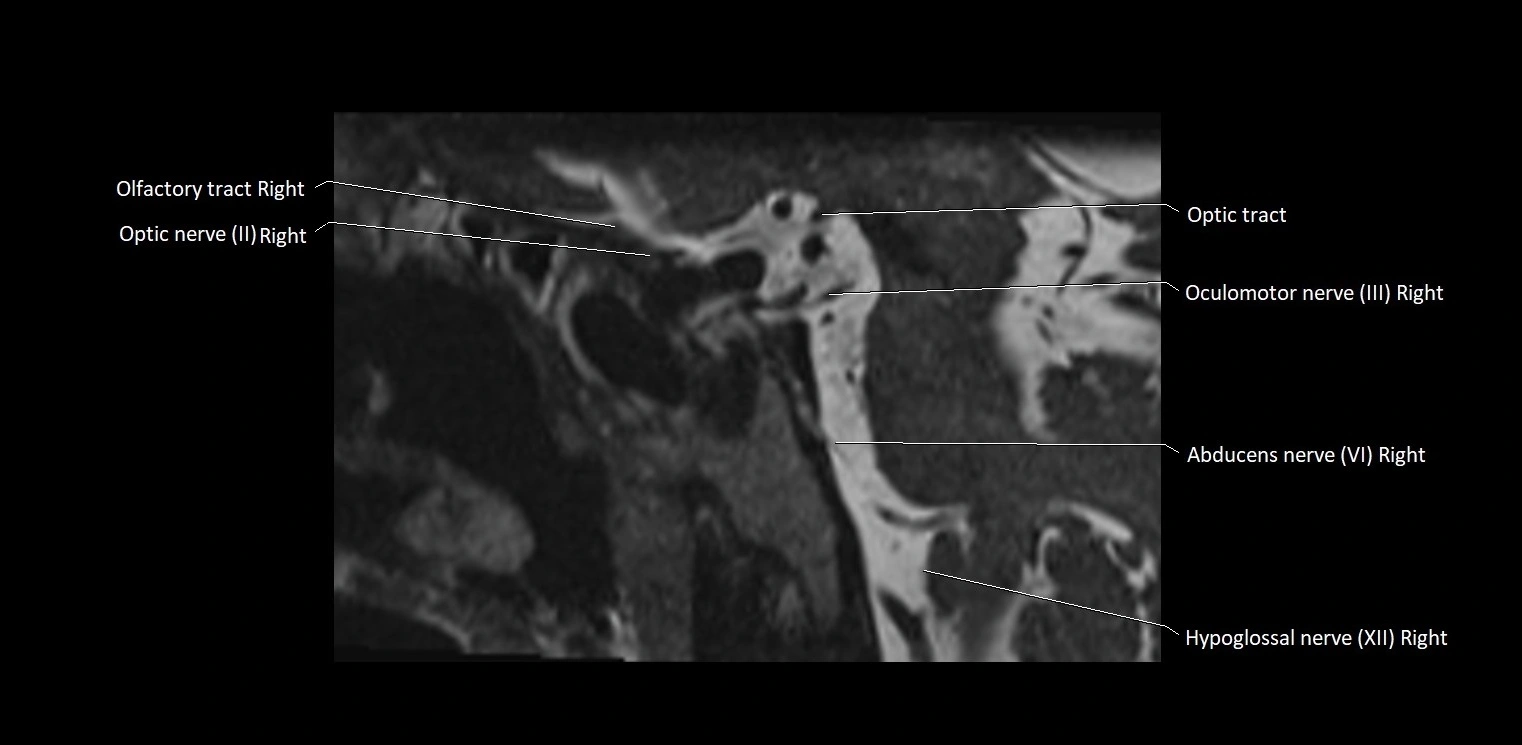

MRI images

image